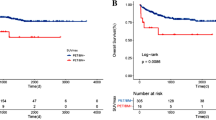

Prognostic factors of PFS and OS

In this set of patients, the median SUVmax was 11.4 (range, 1.5–41.4). The optimal SUVmax cut-off value was 9.5 determined by ROC analysis (AUC = 0.698). Using this cut-off value, all patients were divided into high SUVmax (SUVmax ≥9.5, n = 105) and low SUVmax (SUVmax < 9.5, n = 66) groups. A total of 68 (64.8%) patients in the high SUVmax group experienced treatment failure (progression, recurrence or death), whereas 22 (33.3%) patients in the low SUVmax group experienced treatment failure. The Kaplan-Meier survival curves demonstrated that patients in the high SUVmax group had significantly inferior PFS and OS rates (p < 0.001, Fig. 1). The mean PFS and OS in the high SUVmax group were 32.2 ± 2.8 and 43.2 ± 3.0 months, respectively, and those in the low SUVmax group were 54.9 ± 3.7 and 66.0 ± 3.2 months.

For the 300 bootstrap samples, the C-index values for PFS and OS were 0.729 and 0.736, respectively. The calibration plots for 3-year and 5-year PFS/OS reported good consistency between predicted and observed probabilities for survival time (Fig. 3). To further evaluate the discriminative capacity and clinical use of the models, tertiles of total scores calculated from the nomograms were used to classify the patients into three subgroups (Fig. 4). Patients with the lowest predicted 3-year PFS (high-risk group) had worse outcomes (15.8% 3-year PFS) than patients in the low-risk and intermediate-risk groups (80.3 and 43.1% 3-year PFS, respectively) (P < 0.001). Similarly, patients in the high-risk group with the lowest predicted 3-year OS had substantially worse outcomes (37.0% 3-year OS) than patients in the low-risk and intermediate-risk groups (89.2 and 53.0% 3-year OS, respectively) (P < 0.001).